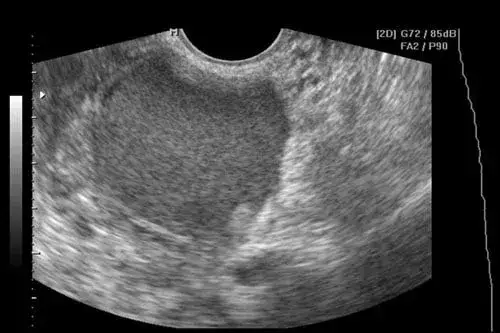

Kiedy zgłosisz się do ginekologa z bólem jajnika, lekarz przeprowadzi kompleksową diagnostykę, aby ustalić przyczynę dolegliwości. Zazwyczaj proces ten rozpoczyna się od szczegółowego wywiadu lekarskiego, podczas którego zostaniesz zapytana o charakter bólu, jego nasilenie, czas trwania, towarzyszące objawy, historię chorób oraz cykl miesiączkowy. Następnie przeprowadzane jest badanie ginekologiczne, które pozwala ocenić stan narządów rodnych. Kluczowym elementem diagnostyki jest USG dopochwowe, które umożliwia dokładne obejrzenie jajników, macicy i jajowodów, a także wykrycie ewentualnych torbieli, zmian zapalnych czy innych nieprawidłowości. W zależności od podejrzeń, lekarz może zlecić dodatkowe badania, takie jak badania krwi (np. morfologia, markery stanu zapalnego, poziom hormonów, test ciążowy) lub badania moczu, aby wykluczyć infekcje dróg moczowych. Pamiętaj, że dokładna diagnostyka jest podstawą skutecznego leczenia, dlatego nie bój się zadawać pytań i dzielić się wszystkimi swoimi obawami.